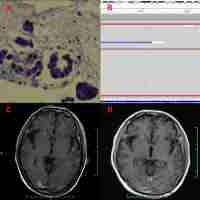

| Abstract | Epidermal growth factor receptor (EGFR) is one of the most promising targets for non-small-cell lung cancer (NSCLC). Icotinib, a highly selective EGFR tyrosine kinase inhibitor (EGFR-TKI), has shown promising clinical efficacy and safety in patients with NSCLC. The exact molecular mechanism of icotinib remains unclear. In this study, we first investigated the antiproliferative effect of icotinib on NSCLC cells. Icotinib significantly inhibited proliferation of the EGFR-mutated lung cancer HCC827 cells. The IC50 values at 48 and 72 h were 0.67 and 0.07 μ M, respectively. Flow cytometric analysis showed that icotinib caused the G1 phase arrest and increased the rate of apoptosis in HCC827 cells. The levels of cyclin D1 and cyclin A2 were decreased. The apoptotic process was associated with activation of caspase-3, -8, and poly(ADP-ribose) polymerase (PARP). Further study revealed that icotinib inhibited phosphorylation of EGFR, Akt, and extracellular signal-regulated kinase. In addition, icotinib upregulated ubiquitin ligase Cbl-b expression. These observations suggest that icotinib-induced upregulation of Cbl-b is responsible, at least in part, for the antitumor effect of icotinib via the inhibition of phosphoinositide 3-kinase (PI3K)/Akt and mitogen-activated protein kinase pathways in EGFR-mutated NSCLC cells. |